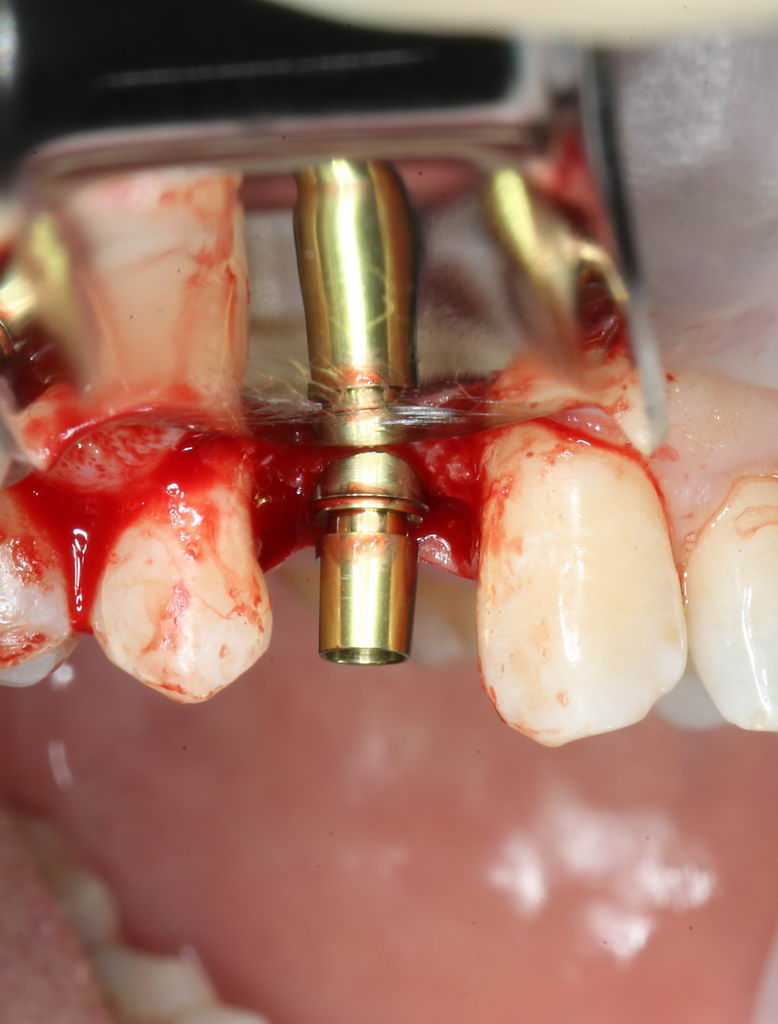

К примеру, мы еще не доделали лунку под имплантат, но уже можем представить, каким образом на на него будет фиксироваться абатмент:

будущего имплантата определён как 3.8 мм. Подробнее о подборе имплантатов можно почитать здесь>>.

Далее, коль ось лунки задана правильно, нам остаётся лишь довести лунку до нужного диаметра. Для этого используются основные рабочие фрезы. Первая из них — диаметром 3.0 мм:

после чего — контроль положения с помощью входящих в набор XiVE аналогов имплантатов: